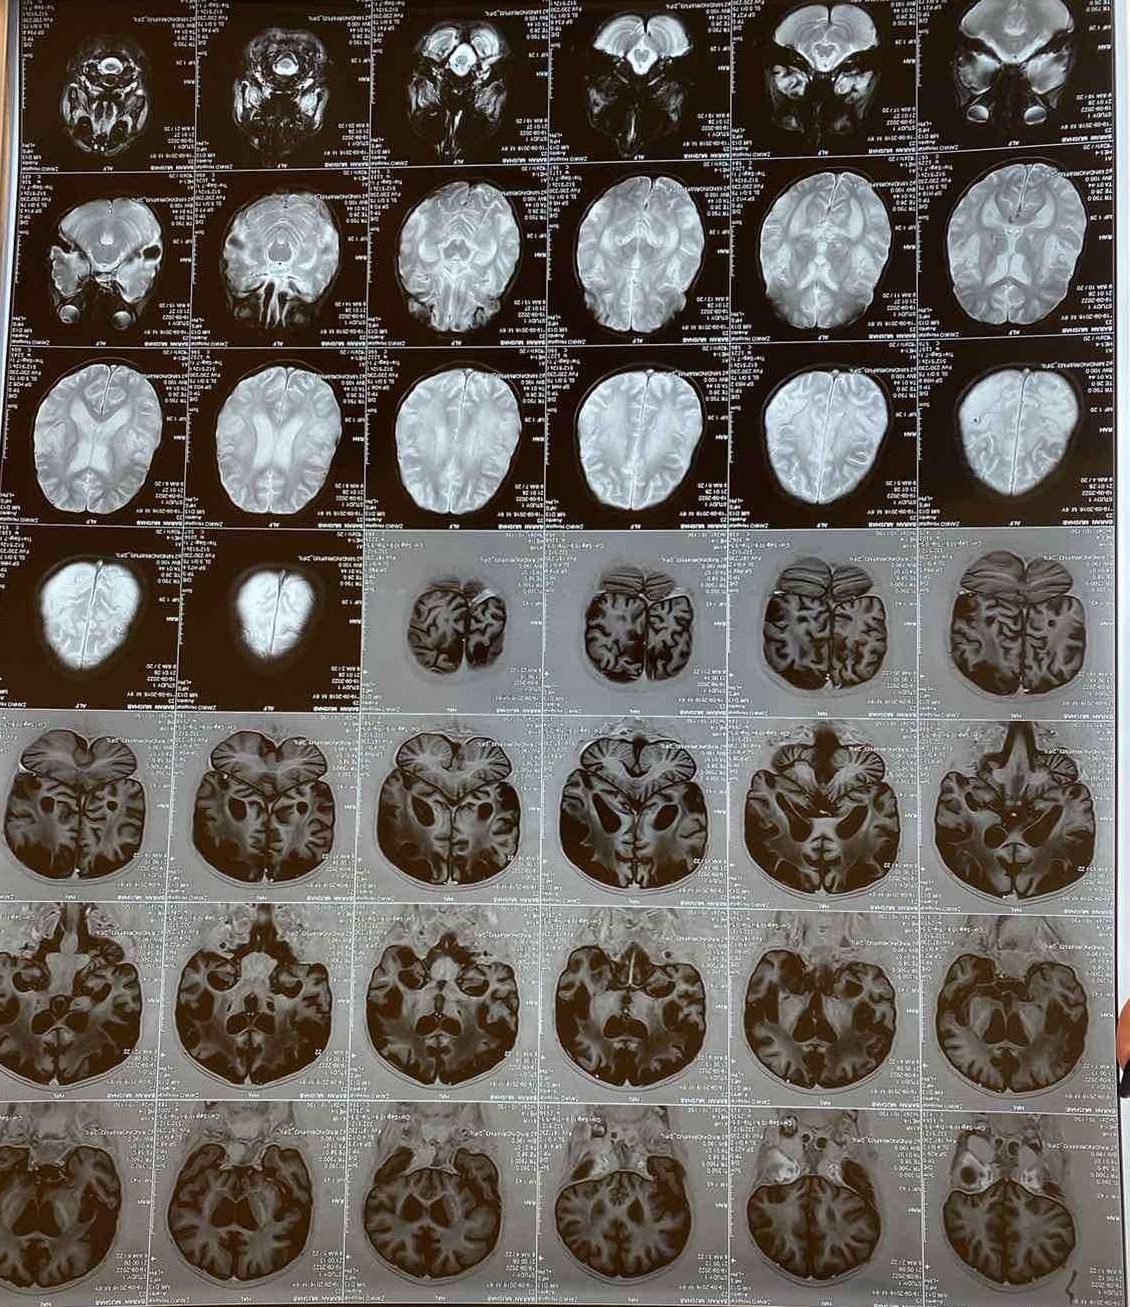

A brain MRI showed bilateral deep white matter cerebral hemisphere increased T2/FLAIR signal (Fig.1). EEG detected diffuse slowing and abnormal epileptic discharge (Fig.2).

Figure 1: MRI showing bilateral deep white matter cerebral hemispheres increased T2/Flair signal and mild brain atrophy.